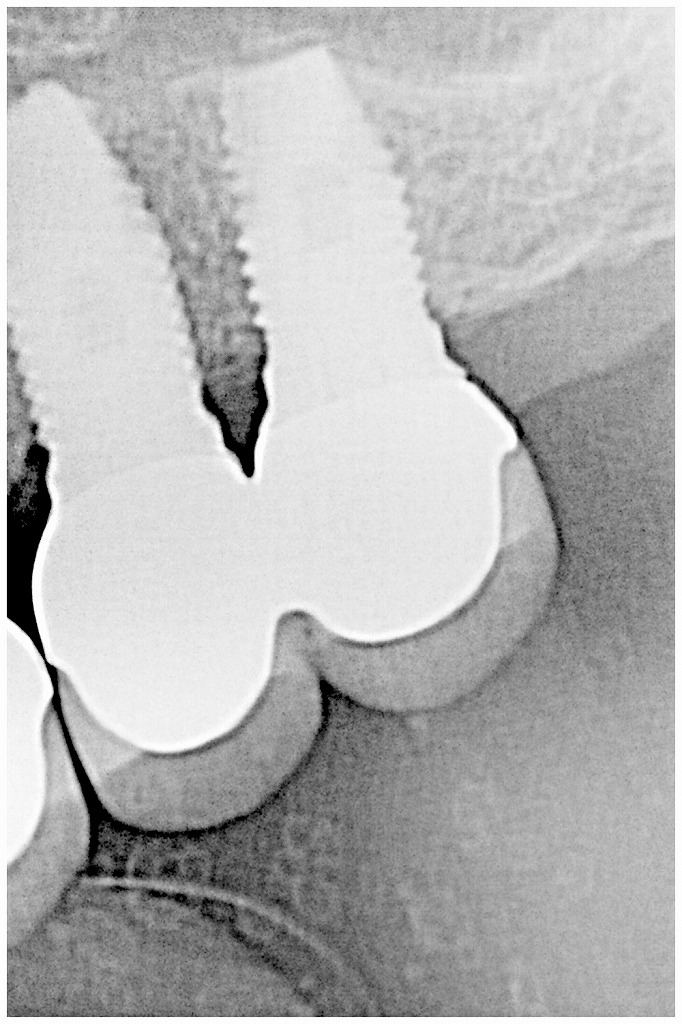

3本ソケットリフトテクニックにより上顎洞を持ち上げ長いいインプラントを埋入していきました

小臼歯大のクラウンが3本入りました

このように清掃性もよいセラミックのインプラント上部構造が作成して入り機能し始めました

上顎洞を持ち上げて長いインプラントを入れた分、しっかりするインプラントとなりました